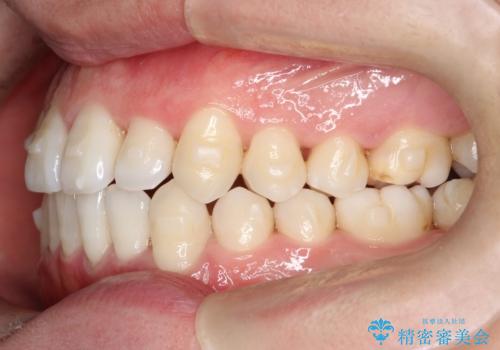

- 前歯のすきっ歯が気になると来院された患者様です。

前歯の隙間をマウスピース矯正(インビザライン)を使用して、閉じていきました。